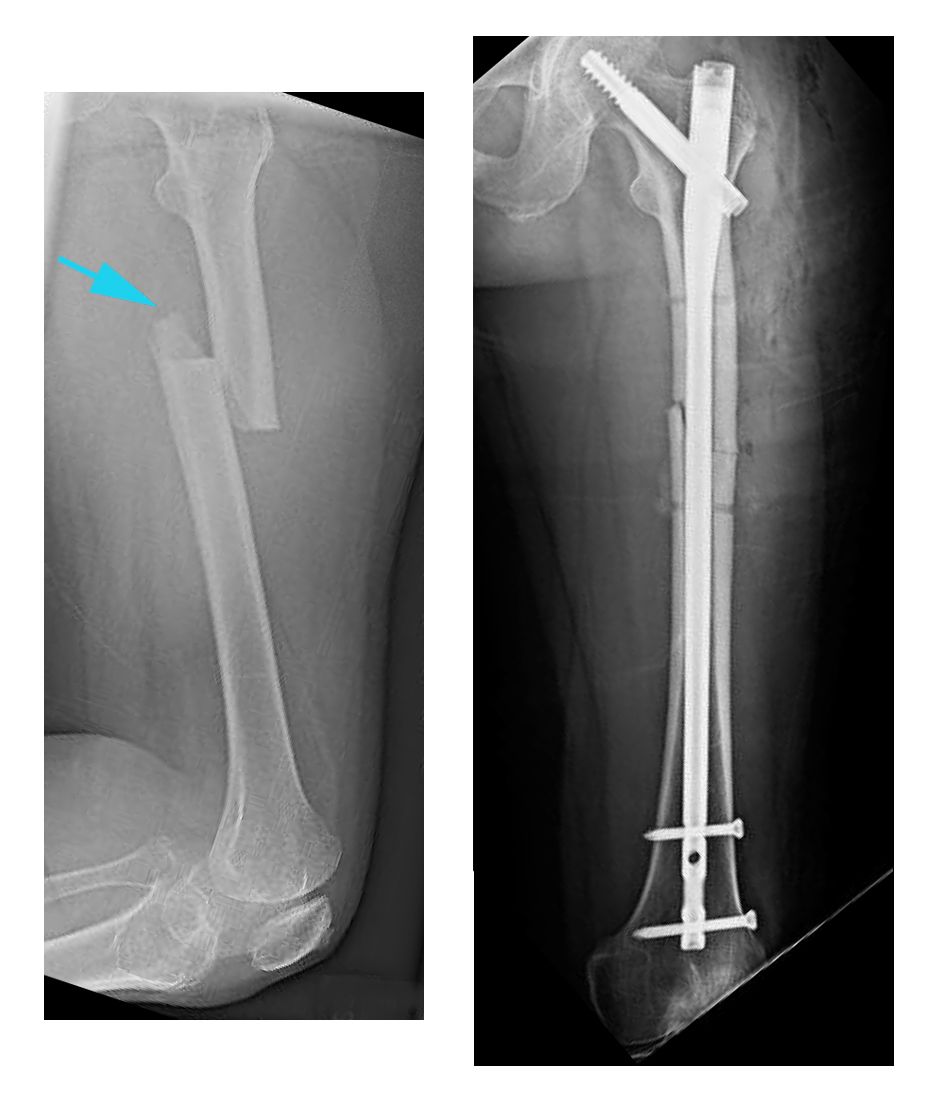

X-rays of transverse fracture and intramedullary nailing

(Left) This X-ray, taken from the side, shows a transverse fracture of the femur. (Right) In this front view X-ray, the fracture has been treated with intramedullary nailing.